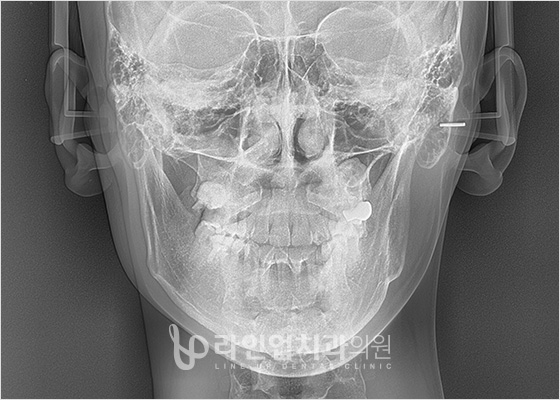

치료전 Before

치료후 After